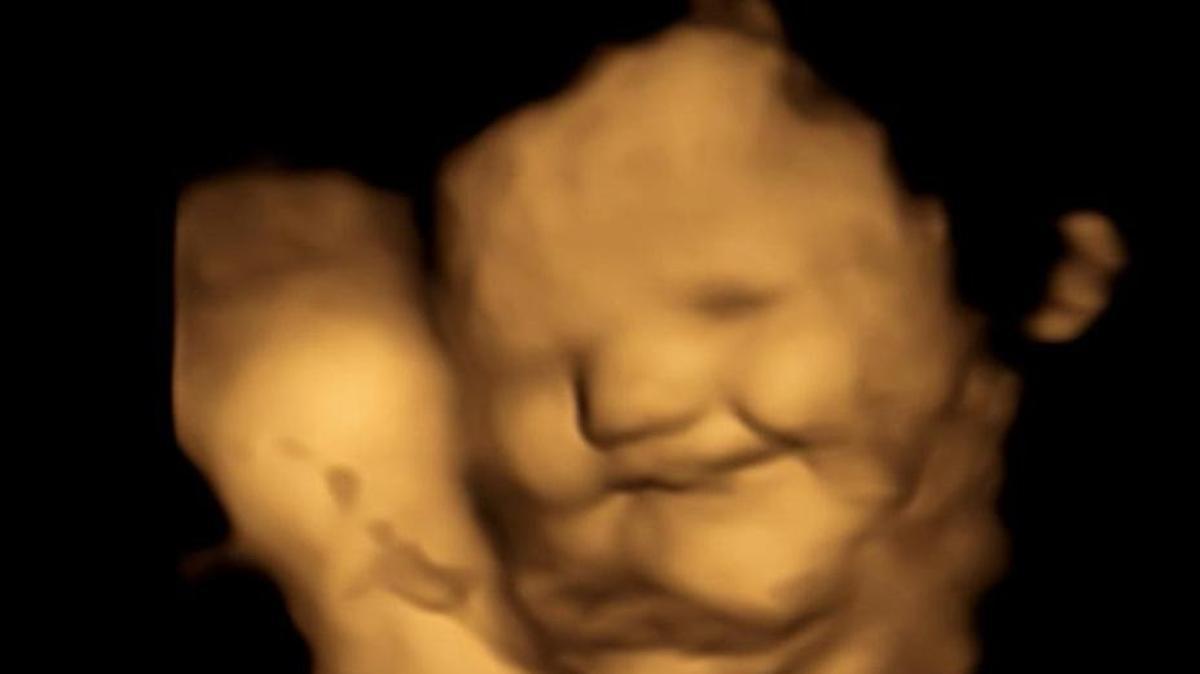

Imágenes de ultrasonido 4D de alta resolución reflejan sus reacciones faciales ante lo que comen sus madres

Con una sonrisa reacciona un bebé no nacido cuando su madre come zanahoria: mejor que la col. / Estudio FETAP.

Imágenes de ultrasonido 4D de alta resolución tomadas a 100 embarazadas revelaron que, cuando comen algo, sus hijos no nacidos pueden olerlo y de alguna forma saborearlo.

Cuando experimentalmente comieron col rizada, los bebés que todavía no han visto la luz reaccionaron haciendo una mueca, pero sonrieron cuando sus madres comieron zanahorias.

Más concretamente, explican los investigadores, los fetos expuestos a la zanahoria mostraron más respuestas de "cara de risa", mientras que los expuestos a la col rizada mostraron más respuestas de "cara de llanto".